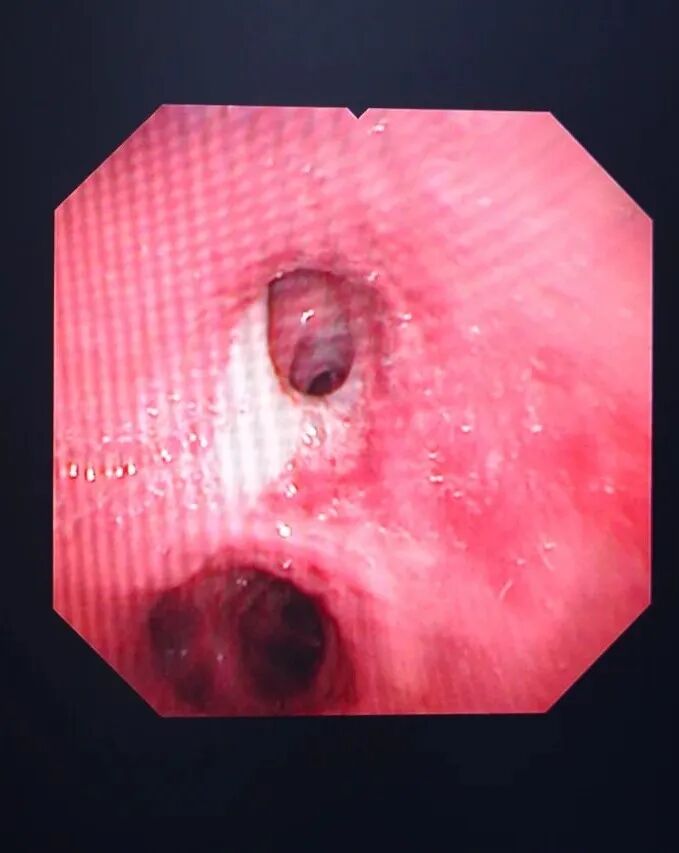

清理气管分泌物

支气管镜检查就是将细长的支气管镜经口或鼻置入患者的下呼吸道,医生可以直观地观察到气管和支气管病变,并根据病变做出判断。是呼吸系统疾病临床诊断和治疗的重要手段,临床应用广泛。